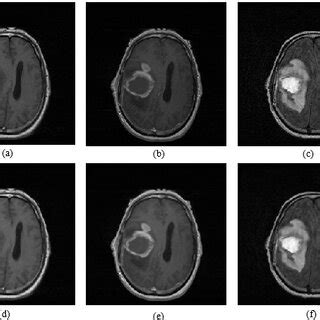

(a) T1 image; (b) T1C image; (c) FLAIR image; (...

Rendering of T1, T1c, T2, and FLAIR at a resolu...

The T1, T2, and T1c magnetic resonance imaging ...